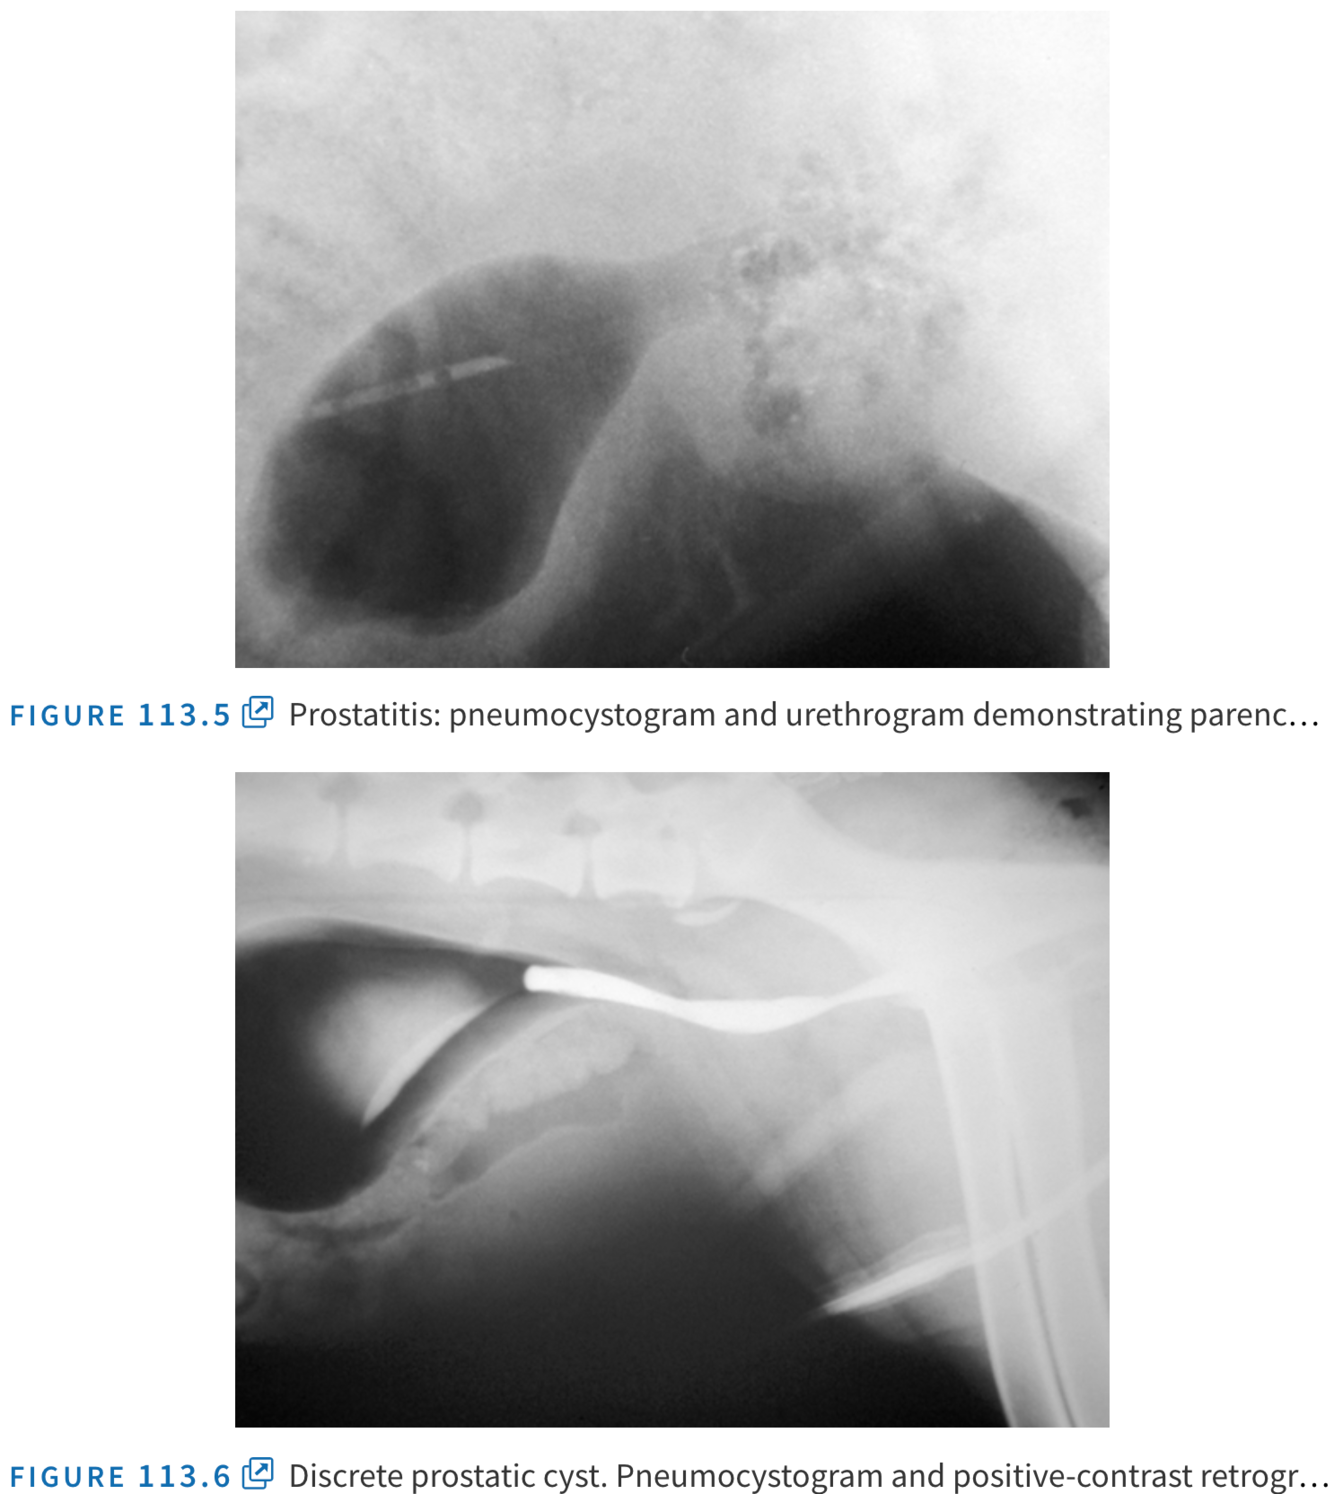

What radiographic chanhes might be seen with prostatic disease and what do they indicate

What is the ultrasonographic appearance in the following conditions

Juvenile haematocysts (under BPH heading) within prostatic parenchyma